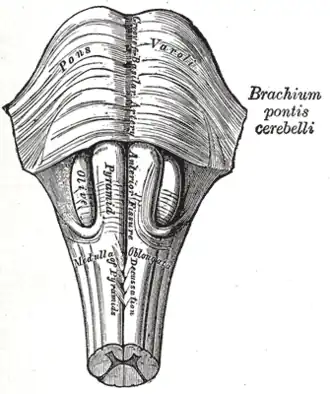

Pons and medulla oblongata. Anterior surface. (Pyramids visible at center.) | |

Medulla oblongata and pons. Anterior surface. (Pyramid visible at center.)

Medulla oblongata and pons. Anterior surface. (Pyramid visible at center.) -